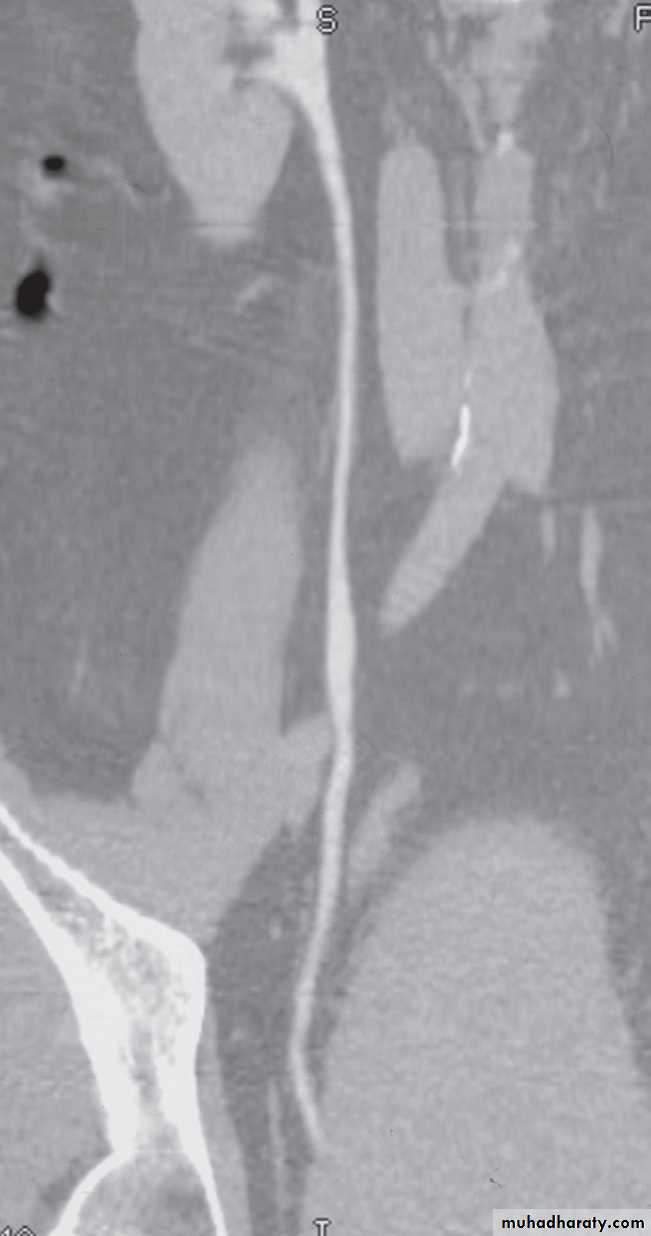

(i) The early renal cortical enhancement phase.(ii) The homogeneous nephrogramphase; and

(iii)The delayed urographic phase, obtained

several minutes later to demonstrate

contrast within the collecting systems.

The normal renal pelvis and pelvi-ureteric junction are funnel shaped. The ureters are usually seen in only part of their length on any one film of IVU because of obliteration of the lumen by peristalsis.Congenital variations of the renal collecting system are relatively common .